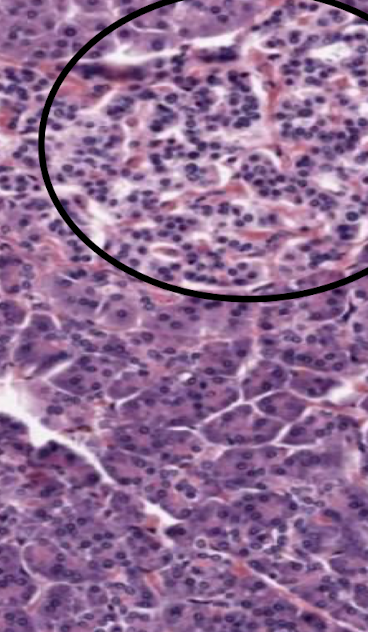

Top portion of the image. Explain the function.

Endocrine pancreas, a pale island/blob in the pancreas. Made of lots of blood vessels for hormones to go to the blood. Cells produce insulin, glucagon, and somatostatin (islands of Langerhaans)

Bottom portion of the image. Classify the tissue.

Exocrine pancreas: vast majority of the pancreas. Contains branched serous acini glands that are full of secretory granules that secrete protein. Purple equates to the rough ER and pink to the lumen/protein secretions.

What is the role of these cells? Classify them, too.

The cuboidal intercalated duct cells extend into the acinus. In these areas, the pale stained cells are termed centro-acinar cells. These cells secrete bicarbonate ions which are important for neutralization of acid in the duodenum.

What is the role of these cells?

Serous cells of the branched acinar glands that are packed full of secretory granules containing digestive enzymes.